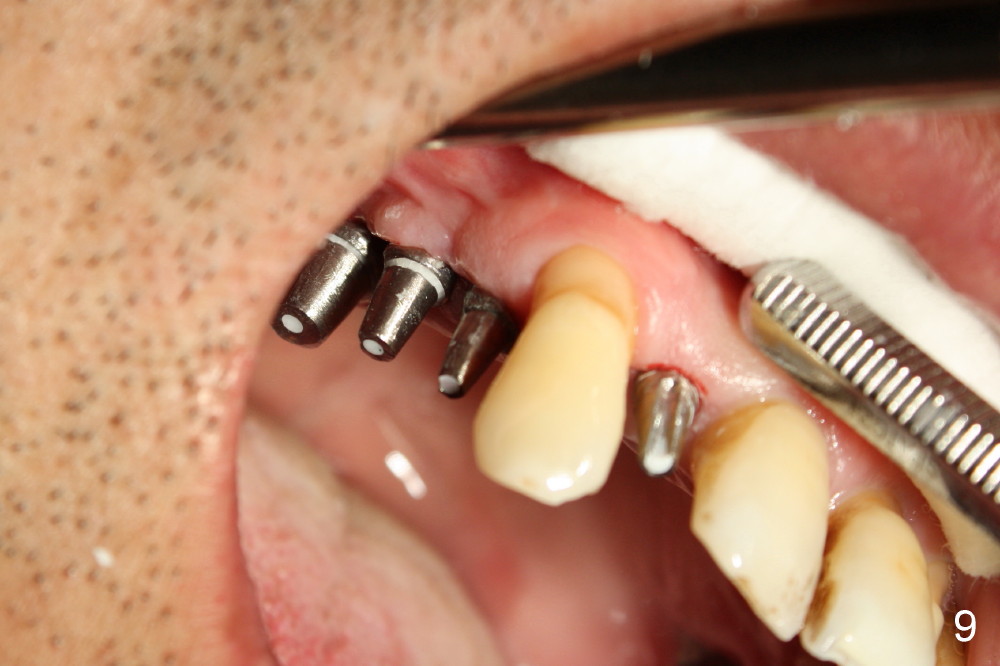

Fig.9 shows 4 uniposts being prepared in 1 appointment yesterday. There happens to be no occlusal reduction on the posts, probably due to history of chronic periodontitis. If I had to cut down posts for occlusion, it would have taken me four appointments.